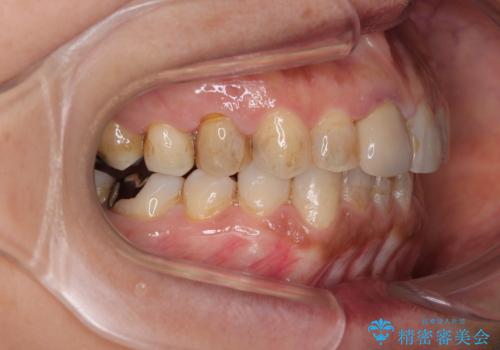

- 上下前歯のデコボコと、治療途中の歯を気にして来院された患者様です。

ご家族がインビザラインにて矯正治療を行っていたため、ご本人の希望によりインビザラインによるマウスピース矯正を行うこととしました。

根管治療が必要な歯は事前に処置を行った上で矯正治療を開始し、概ね歯列が整ったところでセラミッククラウンなどに置き換え、その後インビザラインを1セット使用して仕上げていくこととしました。